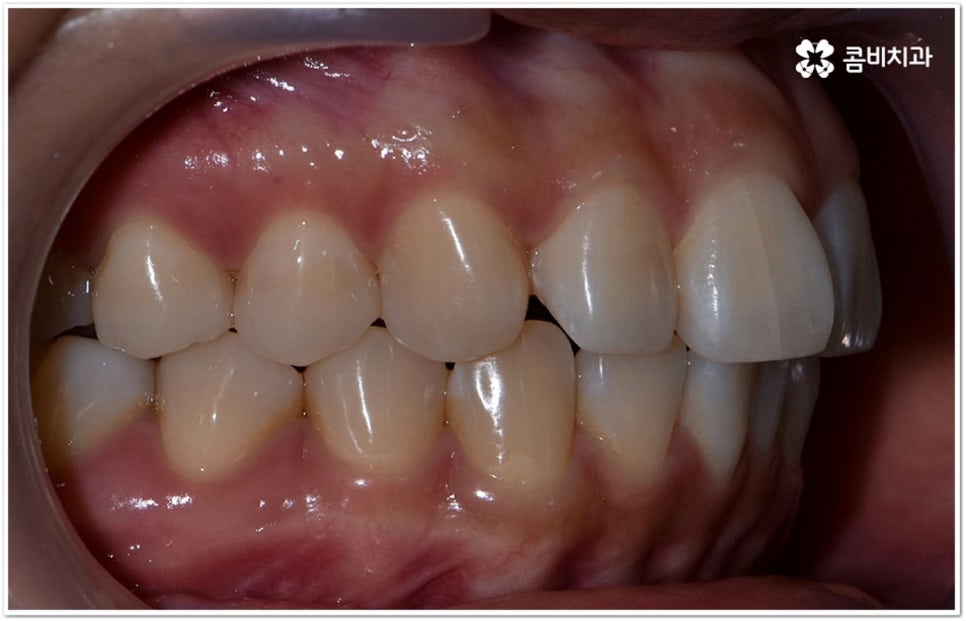

사실 치아가 많이 겹쳐서 삐뚤빼뚤하면 보기에도 좋지 않고 사이사이에 음식물 찌꺼기가 끼어서 충치 같은 구강 질환도 더 자주 발생할 수 있기 때문에 환자분들의 입장에서도 교정 치료를 고려하시는 경우가 많지만, 아주 살짝 덧니가 있을 때는 교정에 대해서 별로 심각하게 생각하지 않으실 수도 있는데요. 이런 덧니는 사람에 따라 오히려 매력 포인트가 될 수도 있기 때문에 스스로 느끼기에 문제가 아니라고 생각한다면 반드시 교정 치료를 해야 하는 것은 아니지만, 만약 입을 벌렸을때 잘 보이는 앞니, 송곳니 등이 덧니라서 웃거나 말을 할 때 신경이 쓰이거나 자기도 모르게 손으로 가리는 습관이 들 정도로 자신감이 떨어진 경우라면 한 번쯤 고려해 보셔도 좋을 거예요. 특히 위아래 맞물림에 문제가 없고 구조적인 부분과 관련된 원인이 크지 않다면 덧니부분교정 을 통해서 보다 빠르고 간편하게 개선이 가능한 케이스도 있기 때문에 꼼꼼한 검진을 통해 자신의 상황이 어떤지부터 알아보시길 권유드리고 있습니다.

덧니의 원인에는 여러 가지가 있는데 대표적으로는 유치가 너무 일찍 빠져서 영구치가 제대로 자리를 잡지 못했거나 턱뼈의 크기와 치아 크기가 조화를 이루지 못하는 경우 등 공간이 부족한 상황을 생각해 볼 수 있어요. 덧니는 주로 송곳니가 가장 흔하나, 치열이 공간이 부족할 경우 이론적으로는 어떤 치아라도 덧니가 될 수 있어요. 이때 원인과 정도를 꼼꼼하게 파악하여 만약 해당 부위만 부분 교정이 가능하다면 덧니부분교정 치료를 할 수 있는데요. 덧니부분교정 을 이용하면 원하는 부위에만 브라켓을 부착하여 치아 이동을 시키기 때문에 전체 교정에 비해서 간편하며 치료 기간도 6~8개월 정도로 줄어들고 통증도 많이 감소될 수 있습니다. 비용적인 부담도 덜하며 (삐뚤어진 정도나 상태에 따라 다르겠지만) 보통 덧니부분교정 의 경우 비발치 과정으로 진행되기 때문에 환자분들의 입장에서는 덧니부분교정 을 많이 선호하시는 편이라고 할 수 있어요. 상황에 따라 미니스크류, 치간삭제, 악궁확장장치 등 환자에게 맞는 비발치 방법을 이용하여 도움 받을 수 있습니다.